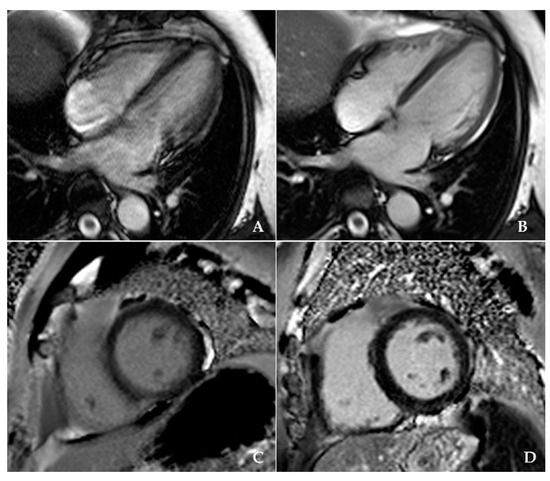

| Image Quality (1 bad, 2 moderate, 3 very good, 4 excellent) | 1.62 ± 0.49 | 3.46 ± 0.51 | <0.001 |